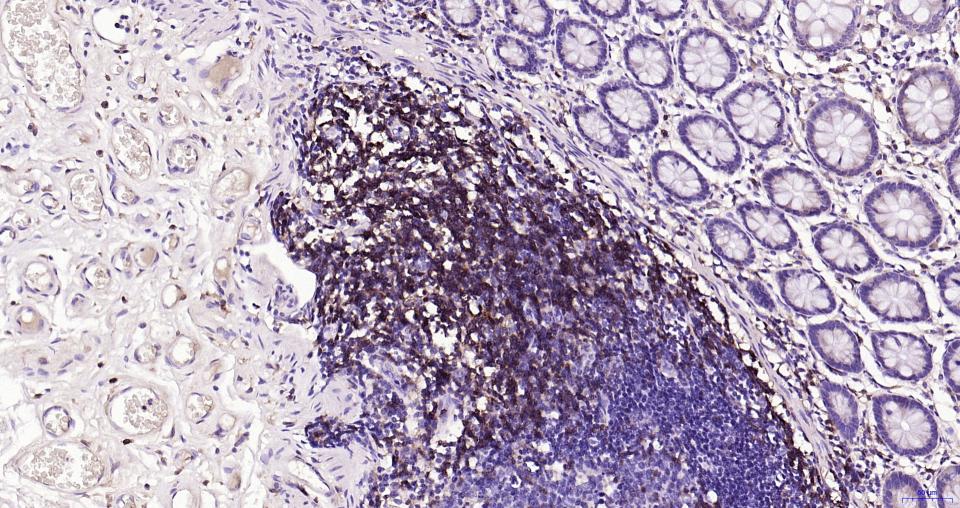

| IHC-P | Human | 1:100-500 | |